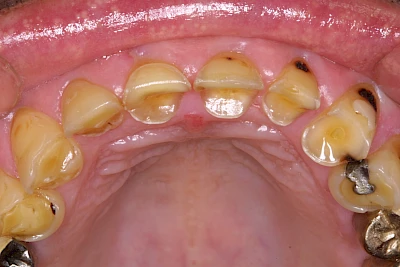

Auswaschung

Auswaschung (Erosion) dagegen ist eine Verschleißerscheinung der Zähne aufgrund von immer wiederkehrenden Säureangriffen durch die Nahrung, verstärkt zum Beispiel durch den Genuss säurehaltiger Getränke oder Speisen. Auch bei Menschen mit einer Essstörung (z. B. Bulimie) können die Zähne durch die Magensäure ausgewaschen erscheinen.